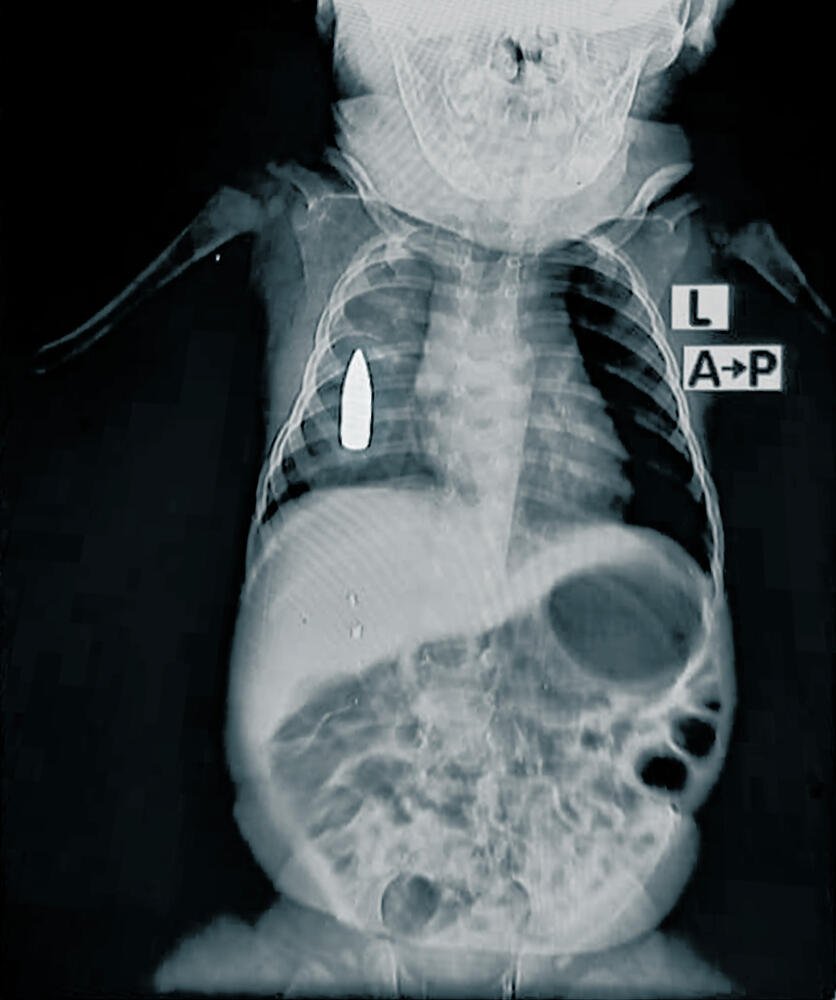

وفي هذا الصدد، يقول رئيس الفريق الطبي في أطباء بلا حدود، الدكتور معين : “أُحضر الطفل رياض البالغ من العمر 18 شهرًا إلى قسم الطوارئ بعد أن أصابت رصاصة طائشة جنبه الأيمن حين كان نائمًا في بيت أهله. وكافح الفريق الطبي لمدة أربع ساعات لتحقيق استقرار حالته. وبسبب فقدانه الكثير من الدم، كان احتمال نجاته من الجراحة نحو 50 %”.

وقال إن تمكن الفريق من وقف النزيف ولكن بقيت الرصاصة في صدره. ومن غير الواضح بعدُ متى سيمكن فعل أي شيء حيال ذلك. يُشار إلى أنّ المستشفى لا يمتلك قدرات جراحية متقدمة، ويرجع ذلك جزئيًا إلى الحظر المطَّرد على إرسال الإمدادات الجراحية منذ أكتوبر 2023. كما أن إحالة المرضى إلى خارج المنطقة أمر صعب للغاية لأن طرق النقل إما مدمرة أو شديدة الخطورة. ورياض هو واحد فقط من بين 314 طفلاً عولجوا من جروح ناجمة عن طلقات نارية وانفجارات في عام 2024.

رياض هو طفل يبلغ من العمر 18 شهرًا كان قد أُصيب برصاصة طائشة في صدره أثناء قيلولته في الخرطوم. نُقل رياض إلى غرفة الطوارئ في مستشفى بشائر التعليمي الذي تدعمه منظمة أطباء بلا حدود من قبل مقدمي الرعاية. بدأ فريق جراحة الطوارئ التابع لمنظمة أطباء بلا حدود في إجراء عملية جراحية لإنقاذ حياة رياض وتمكن الجراحين من إنقاذ حياته لكن الرصاصة بقيت في صدره. السودان، في نوفمبر 2024.